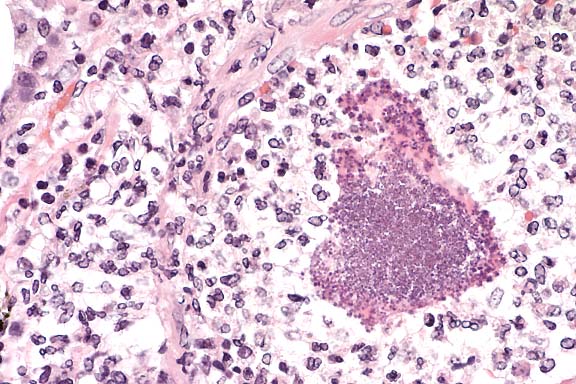

Case 27-1. Lip. The inner surface shows a vesicle containing necrotic acanthocytes and multincleated syncytial cells with diffuse, vague amphophilic nuclear inclusions. 20X

1. Lip: Degeneration and necrosis, epithelial, multifocal, with vesicles, syncytia, vasculitis, and epithelial and endothelial eosinophilic intranuclear inclusion bodies, cynomolgous monkey (Macaca fascicularis), primate.

2. Minor salivary glands: Sialoadenitis, lymphoplasmacytic, diffuse, mild to moderate.

In contrast to the gross skin lesions, the microscopic lesions are relatively mild and include degeneration and necrosis of surface and adnexal epithelium and vesicle formation. Intranuclear viral inclusions are present in almost all affected epithelial foci. A mild variable neutrophilic infiltrate and multifocal subcuticular hemorrhage are present in the dermis of some affected sections. In sections with subcutaneous hemorrhage, small vessels are congested, lined by rounded endothelium and contain occasional fibrin aggregates. Some vessel walls are necrotic and rare endothelial cells contain intranuclear inclusions. Similar vascular lesions are present in the spleen.